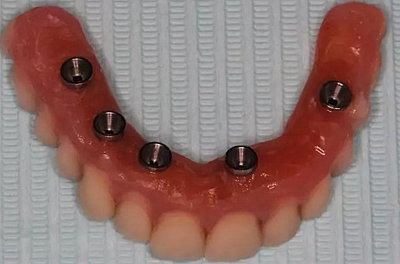

牙列缺失患者由于支持、固位、穩(wěn)定不足導(dǎo)致義齒效果差,如果在牙槽嵴內(nèi)植入種植體,種植體可以根據(jù)種植體數(shù)量不同提供義齒不同程度的固位、穩(wěn)定、支持,獲得不同的修復(fù)效果。當(dāng)單頜牙列缺失患者使用1-2顆植體,植體和覆蓋義齒之間可以靠一些附著體如磁性附著體、桿卡式附著體、球帽式附著體等裝置連接,主要提供固位和穩(wěn)定作用,少量的支持作用,當(dāng)單頜牙列缺失使用4顆植體時(shí),很大部分支持力可以由植體承擔(dān),當(dāng)使用4顆以上植體時(shí)可完全由種植體提供義齒的支持、固位和穩(wěn)定,甚至制作為不可摘戴的全口固定種植義齒。

1、種植固定修復(fù)后,義齒的基托面積大大減小,從而大大提升了患者的舒適度,同時(shí)惡心、發(fā)音障礙也大大減輕;

2、種植固定修復(fù)采取的是種植體支撐,或者種植體+粘膜支撐的受力方式,咀嚼效率比全口義齒提升很多,通俗來講,也就是老年人基本可以正常進(jìn)食,有利于老年生活的豐富和身體機(jī)能的保持;

3、種植固定修復(fù)因?yàn)橛蟹N植體的支撐,可以在一定程度上延緩牙槽骨的骨吸收,從而使義齒的使用年限更長;